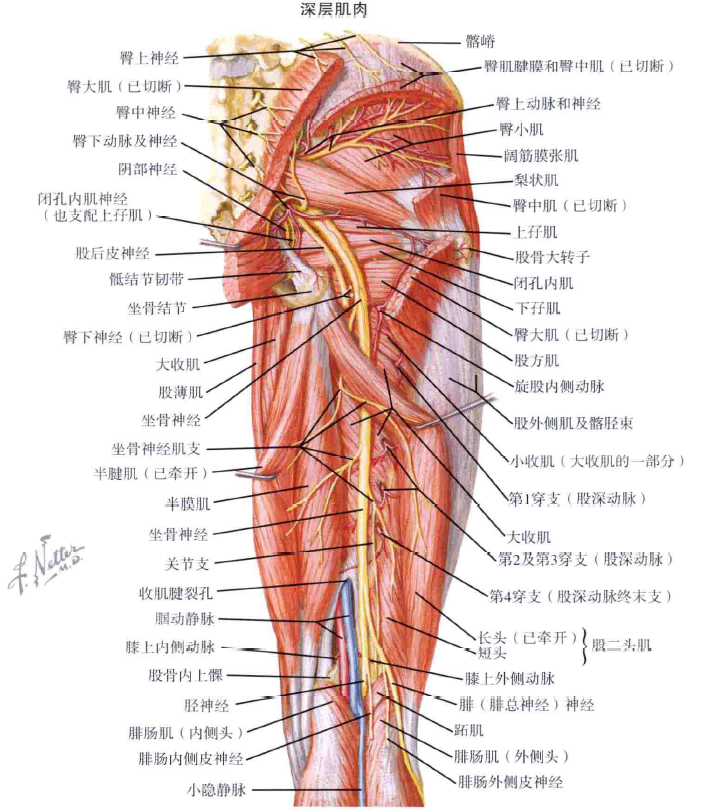

其次,大家可以看看髋关节周围重要的肌群、血管神经:

右侧髋关节-后方-重要肌群及血管神经